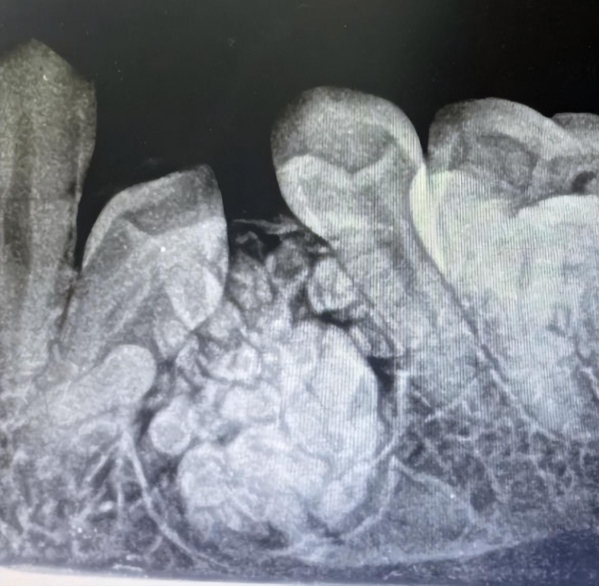

医生安排拍了个口腔全景片,医生发现女孩患有牙瘤。

需要进行全麻手术,手术结束后,医生告诉女孩的家人一共拔除了57颗牙。